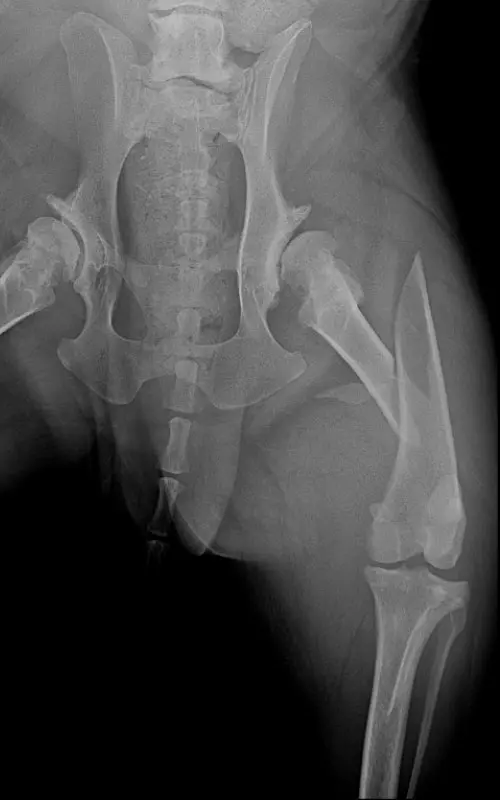

In our case, a 10-year-old labrador is involved in a car accident and his left femur and right tibia are severely injured. The dog had difficulty moving anyway due to severe hip arthrosis. During one surgical narcosis, K-pin - polyaxial locking plating was applied to both bones, the larger fragments were also fixed with 1-1 lag screws.